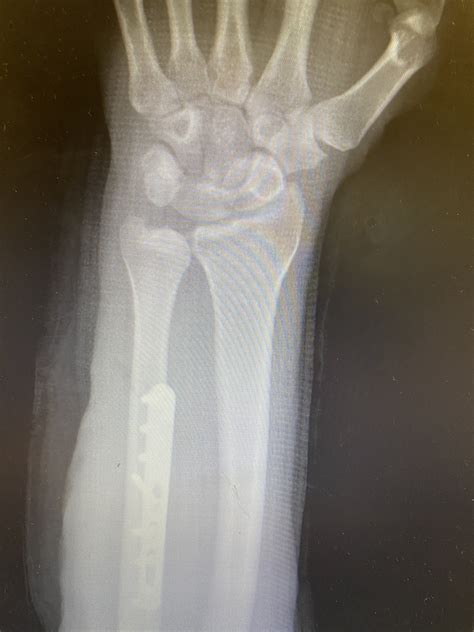

• Ulnar Shortening Osteotomy: A procedure where a small section of the ulna bone is removed, and the bone is fixed back together with a plate and screws to shorten it, effectively creating more space in the wrist.

The recovery timeline varies significantly based on the severity of the condition and the intervention chosen. Following surgery, patients are typically placed in a cast or splint for several weeks, followed by a rigorous physical therapy program. Most individuals return to normal activities within three to six months. The long-term prognosis is generally positive, provided that the patient adheres to post-operative restrictions and gradually reintroduces load to the wrist.